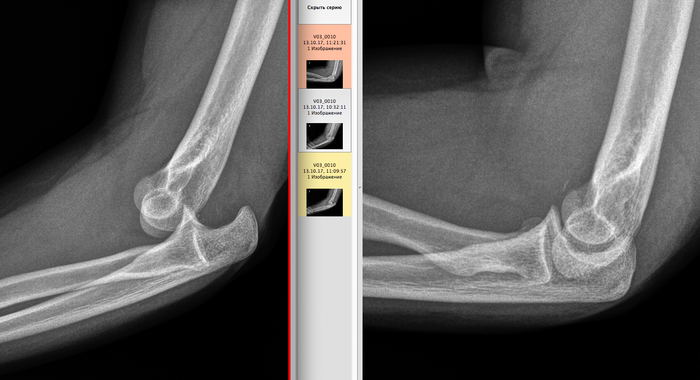

История 3

Задний вывих предплечья. На контрольной рентгенограмме справа вывих отсутствует.